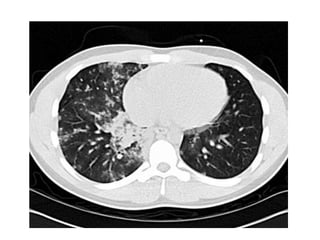

HAPE

Above 4500 m (14,760 ft)

Pathophysiology               Clinical

• Severe pulmonary            • 2 – 4 days after arrival

Hypertension                • SOB

• Some areas pulmonary        • Cough

vascular bed overperfused   • Hemoptysis

• Blood vessel injury         • Dx

• Fluid leak into lung           – Crackles

• Lung edema – water             – Xray

– Worsens gas exchange

HAPE Above 4500 m (14,760 ft) Pathophysiology Clinical • Severe pulmonary • 2 – 4 days after arrival Hypertension • SOB • Some areas pulmonary • Cough vascular bed overperfused • Hemoptysis • Blood vessel injury • Dx • Fluid leak into lung – Crackles • Lung edema – water – Xray – Worsens gas exchange